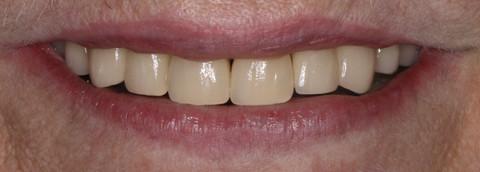

We decided to improve her smile with crowns on all her upper teeth as veneers are not an option for a person who is a bruxist (grind /clench their teeth), and lower teeth we built up with composite (white filling) and 2 implants on either side to help the patient eat properly.

After Treatment - Upper crowns Metal Ceramic , lower anterior composite to close spaces in between and premolar as linked implant bridges.